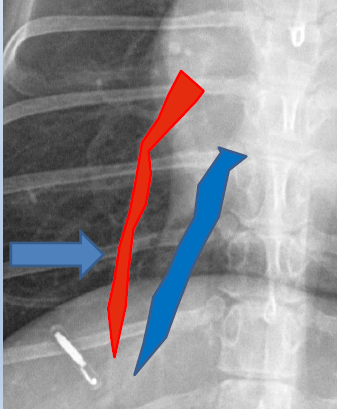

Caudal mediastinal reflection

Caudal mediastinum

Caudal vena cava

Cranial mediastinum

Cranioventral mediastinal reflection

Descending aorta

Esophagus

Red Cupula

Blue Crura